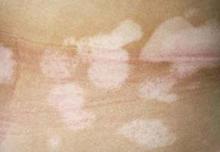

白癜风病虽不痛不痒,但侵蚀着患者健康的肌肤和心灵,严重损坏人的容貌,挫伤人的精神,影响正常生活、婚姻、工作和社交,是世界性难治病之一。白癜风常见的发生部位是:面部、颈部、腰带处、骶尾部、指趾背部,女性胸罩带子或纽扣压迫处,疝托支撑处、肛门口、女性会阴部。推荐阅读:治疗白癜风需要多少钱

白癜风是一种病因尚未完全明确的后本性色素缺乏症。多数学者认为该病的发生是由于表皮与真皮之间的黑色素细胞内酪酶系统功能减退或丧失,引起局部黑色素细胞减少或失去活性,从而生成黑色素量减少而引起的。